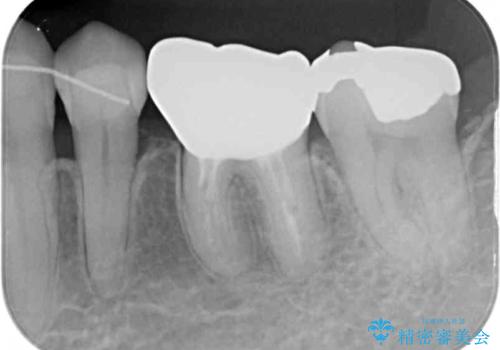

上唇小帯を切除したことで、ブリッジのダミー部分に触れて腫れていた歯肉は健全な状態になりました。

隙間もなくなったことで話す際の空気の漏れや、ものが挟まることもなくなりました。